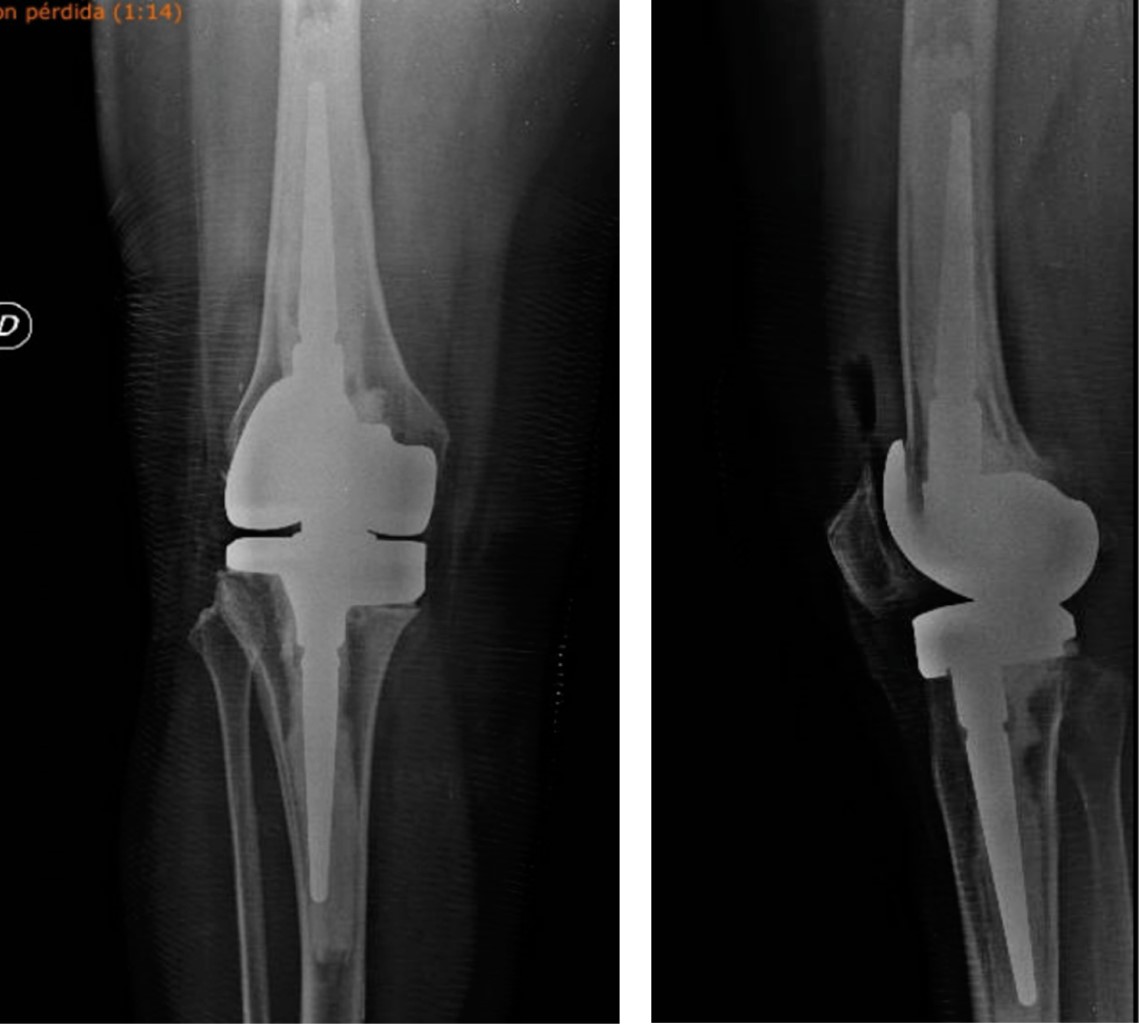

Figure 3

Figure 4